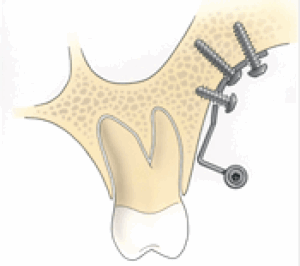

De platen zijn stevig bevestigd met 2 (in de onderkaak) of 3 (in de bovenkaak) schroeven op een veilige afstand van de wortels van de tanden. Meestal worden de bovenste platen met monocorticale schroeven, 2,0mm diameter en 5mm lengte voor de onderste schroeven en 7mm lengte voor de bovenste schroef op de infra-zygomatische top van de bovenkaak gestoken. In de onderkaak worden de platen meestal tussen de hoektand en de laterale snijtand geplaatst. Voor sommige indicaties kunnen ze ook tussen de eerste molaar en de tweede bicuspide worden geplaatst.

Uniek aan de Bollard botankers is dat ze ‘geprint’ zijn van puur titanium (3D). De Bollard botankers bestaan uit één stuk en zijn zonder buigprocedures gemaakt. Hierbij is er geen gebruik gemaakt van een hittebron, wat het risico op breuken verminderd. De botankers zijn gesteriliseerd en dubbel verpakt.

Bestaat uit een miniplate met 2 of 3 gaten, een verbindingsstang en een bevestigingseenheid met een blokkeerschroef. Het ontwerp van de cilindrische bevestigingseenheid maakt het mogelijk om allerlei soorten draden te bevestigen om verbinding te maken met het vaste apparaat.